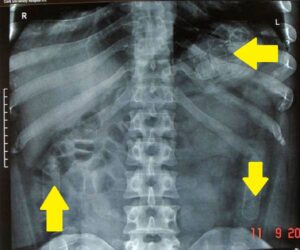

Purtroppo, per lui, l’essere Nigeriano e spostarsi di continuo in aereo, quasi sempre con dei voli last minute, lo rende agli occhi della Polaria un potenziale ovulatore, ovvero un corriere della droga che usa il proprio intestino come contenitore dei famigerati ovuli. Per farla breve l’uomo è stato portato in ospedale per una radiografia di controllo, radiografia che non ha sciolto i dubbi della Polaria e di conseguenza lo ha fatto ricoverare per una terapia “lassativa”.

(Immagine sotto licenza C.C. di J Kelly, M Corrigan, RA Cahill, and HP Redmond )